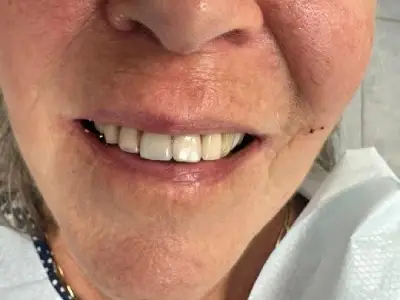

"פליפר" מורכב מבסיס בצבע החניכיים העשוי בדרך כלל מחומר אקרילי או "ואלפלסט" (חומר גמיש ופלסטי), ועליו מורכבות שיניים מלאכותיות בצבע דומה לשיניים הטבעיות שלכם.

ניתן לבצע "כנפיים" ממתכת, אבל אנחנו במרפאת Amazing Smile מעדיפים לבצע מפלסטיק – הדבר הנותן מענה אסתטי יפה יותר. "פליפר" מוחזק בפה באמצעות ווים גמישים שנאחזים בשיניים, וכך מתקבל מראה טבעי ואסתטי.